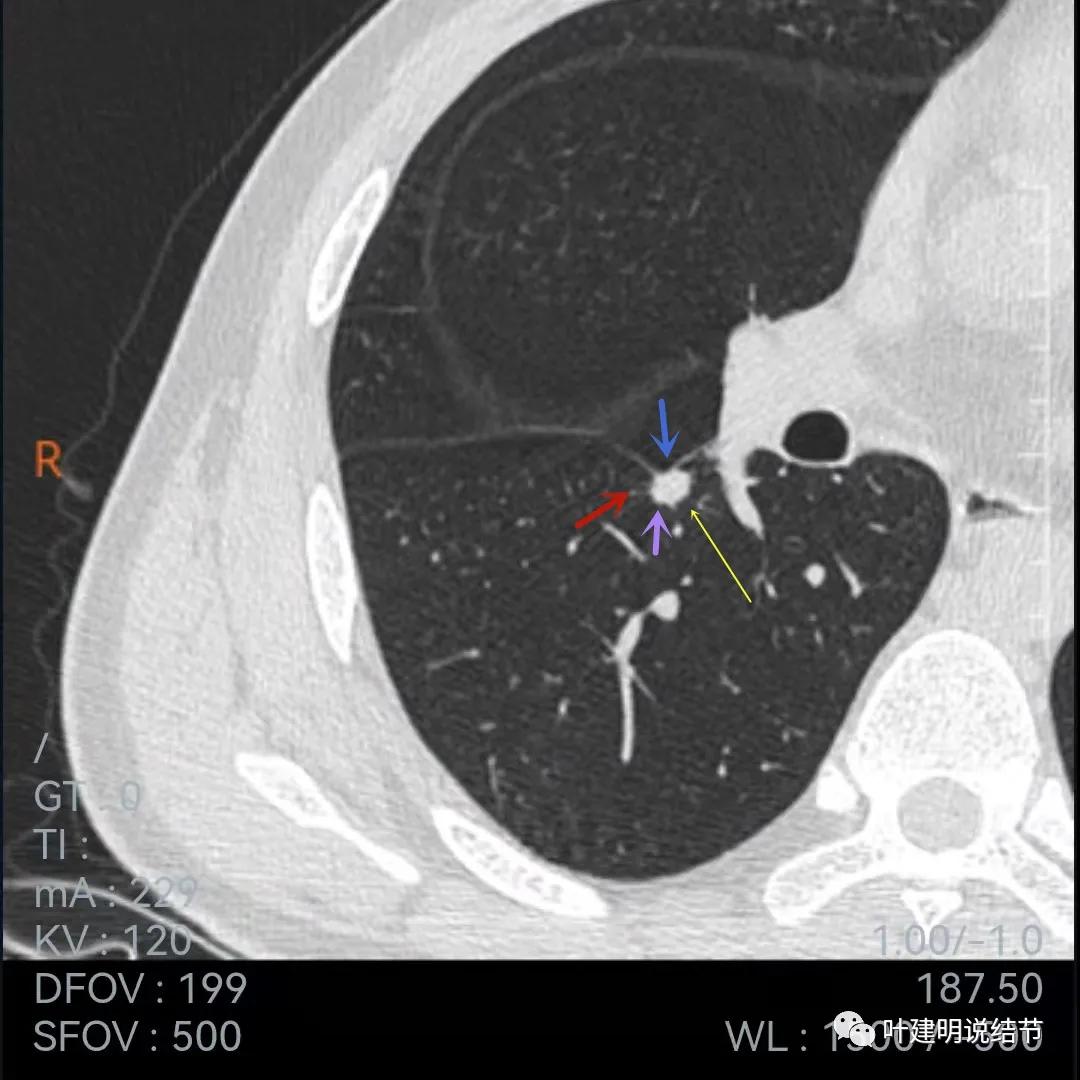

再来看下面薄一点的,也是2020年7月的图像:

叶间胸膜牵拉

牵拉明显

中间密度略低(黄色箭头),前部边缘似有少许毛刺或毛糙的感觉(紫色箭头)

叶间胸膜牵拉凹陷

上图层面密度略不均

与前一年相比,病灶略有不同,感觉边缘粗糙起来,胸膜凹陷较前明显,但因为薄层与非薄层的区别,可比性略差。